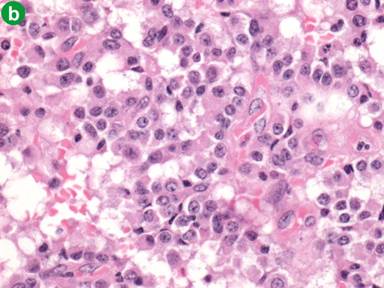

Macroscopically, the ovary was enlarged, measuring 50x40x55 mm, and weighed 55 g. It had a nodular appearance with an intact outer capsule. On sectioning, the ovary contained a multilocular cystic lesion, the largest cystic space measuring 20 mm in diameter. The non-cystic areas of the ovary had a yellow cut surface. Microscopic analysis demonstrated tumour cells with monomorphic nuclei and pale pink cytoplasm arranged predominantly in glandular and trabecular structures (Figure 5ab). Immunohistochemistry showed diffuse expression by tumour cells of cytokeratin 18 and synaptophysin (Figure 5c), with focal expression of chromogranin and cytokeratin 19, and cytoplasmic positivity for glucagon (Figure 5d). Overall the appearances indicated a neuroendocrine tumour, and were compatible with an ovarian metastasis from the original glucagonoma. The patient remains well at 16 months follow-up after oophorectomy, and with no evidence of any further metastatic disease (now more than 6 years after laparoscopic resection of the primary glucagonoma).

Figure 5. Photo microscopy from the resected ovarian specimen. a. This panel shows a low power view stained with haematoxylin and eosin (H&E; total magnification x40). The tumour is shown with the black arrow and ovarian cortex with yellow arrow. b. This panel is a high power view of the tumour cells, confirming the neuroendocrine appearance (H&E; total magnification x200). c. Section stained with synaptophysin which is a marker of neuroendocrine differentiation (total magnification x200). d. Section of tumour stained with glucagon, in keeping with metastatic glucagonoma (total magnification x200). |